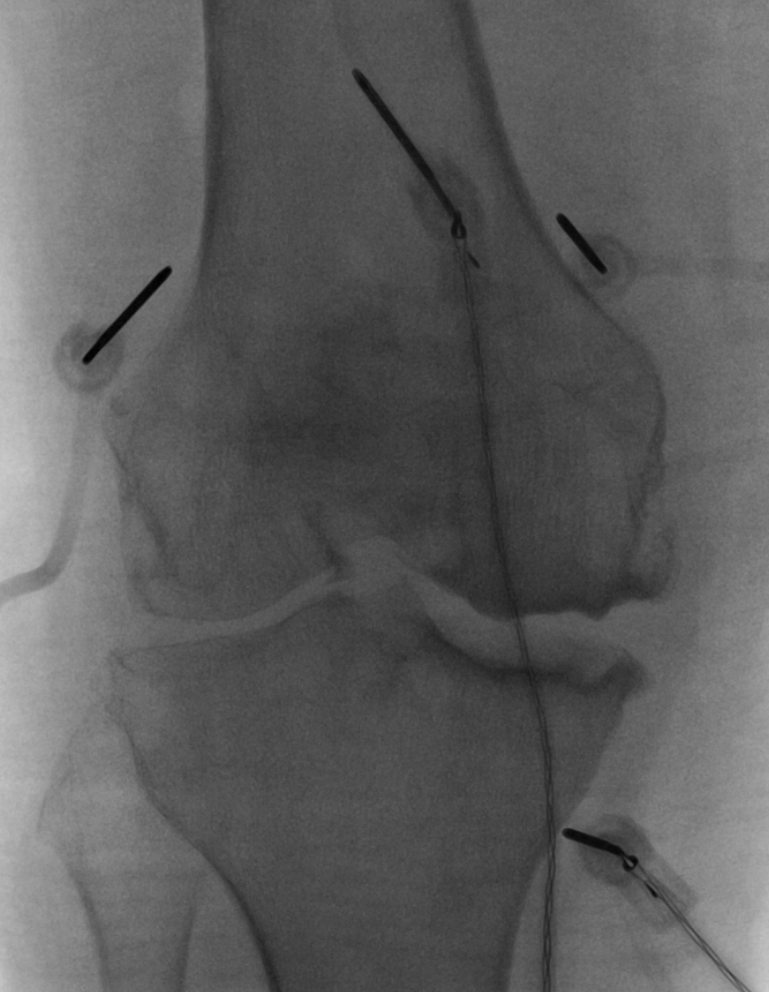

Unlike knee replacement surgery, GNA is minimally invasive. In this procedure, a probe delivers radiofrequency energy into the nerves surrounding the knee joint. These nerves are responsible for transmitting the pain signal. By disrupting this process, GNA alleviates the patient’s pain.

“There are currently three types of radiofrequency ablation instruments,” explains Dr. Symanski. “Here at UW, we use cooled radiofrequency ablation, a newer-generation technology, which is able to ablate a larger amount of tissue. This should theoretically lead to better outcomes, like more pain relief and longer-lasting pain relief.”